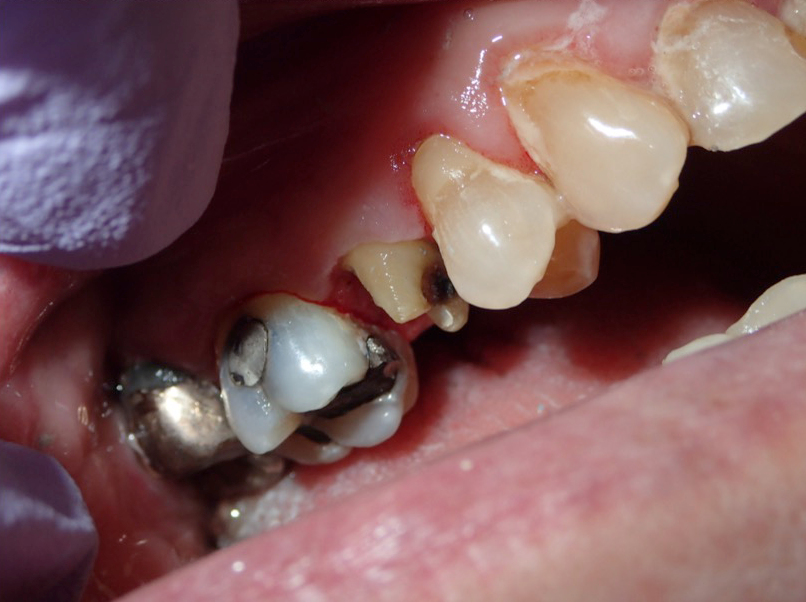

Fig 6. Tooth preparation has been completed.

Figure 6

Figure 6 through Figure 9 demonstrate the use of retraction paste and a cap. An upper bicuspid was prepared (Figure 6), and some bleeding occurred due to the clinician working below the existing restorations. Retraction paste was then applied (Figure 7), but there was still some residual bleeding. The clinician then had the patient close on the retraction cap to stop the bleeding (Figure 8). Some blanching occurred as the patient bit into the cap. The patient will hold that position depending on how much bleeding occurs. Figure 9 shows the exposed margin ready for impressioning. In this case, the retraction cap was kept in place with the patient biting down on it for 2 to 3 minutes instead of 1 to 2 minutes because there was a fair amount of bleeding initially.

Figure 10 through Figure 12 are examples of final impressions taken with retraction paste alone. No cord or soft-tissue diode laser was used. Figure 10 shows an impression on which the clinician went quite far subgingivally and achieved a clean margin, including an excavated area on the labial surface. These examples demonstrate how consistent the use of retraction paste can be.